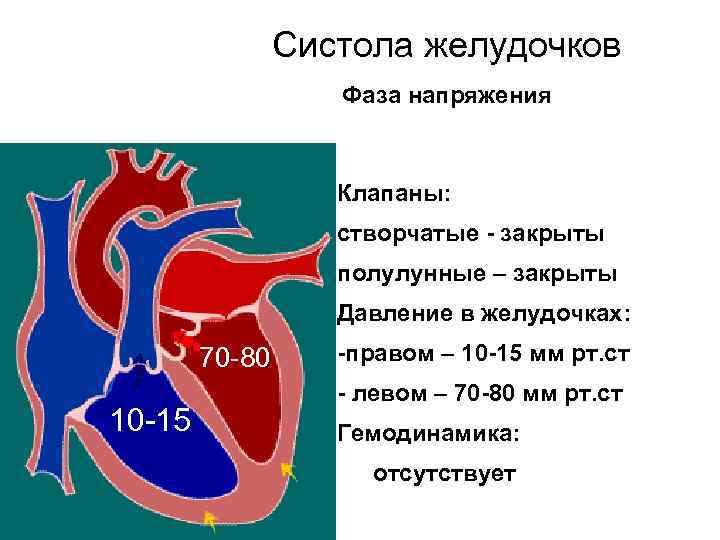

Систола желудочков Фаза напряжения Клапаны: створчатые - закрыты полулунные – закрыты Давление в желудочках: 70 -80 10 -15 -правом – 10 -15 мм рт. ст - левом – 70 -80 мм рт. ст Гемодинамика: отсутствует

Систола желудочков Фаза напряжения Клапаны: створчатые - закрыты полулунные – закрыты Давление в желудочках: 70 -80 10 -15 -правом – 10 -15 мм рт. ст - левом – 70 -80 мм рт. ст Гемодинамика: отсутствует